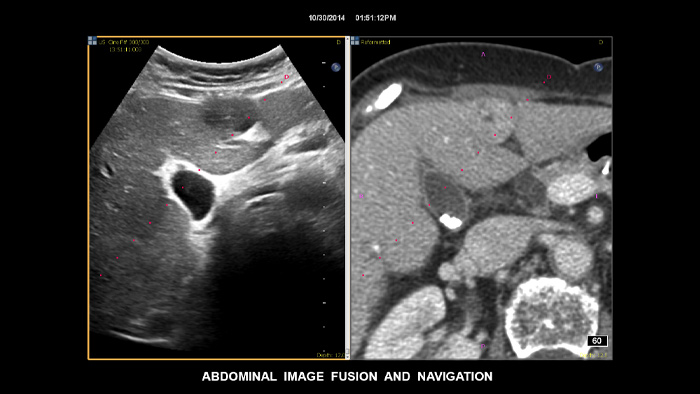

Prendi decisioni sicure anche in casi diagnostici complessi grazie alla fusione delle immagini e alla navigazione dell'ago di Philips. Il flusso di lavoro semplificato consente ai medici di ottenere una fusione rapida ed efficace di immagini TC/RM/PET con ecografia dal vivo, mentre la navigazione dell'ago aiuta a guidare la biopsia di lesioni di piccole dimensioni e di difficile accesso2.